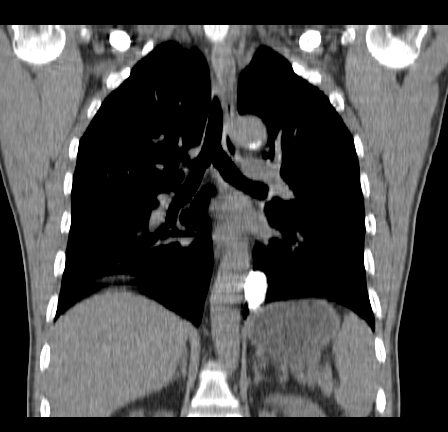

以下是引用影像孺子牛在2009-5-20 23:18:00的发言:[br]左侧后心膈角处类椭圆形钙化灶,最常见的是淋巴结钙化,但太大了不支持,其它如食管囊肿钙化、实性畸胆瘤等。何东西钙化真不好定。

以下是引用zbp537在2009-5-20 20:52:00的发言:[br]钙化灶,来源不好说。